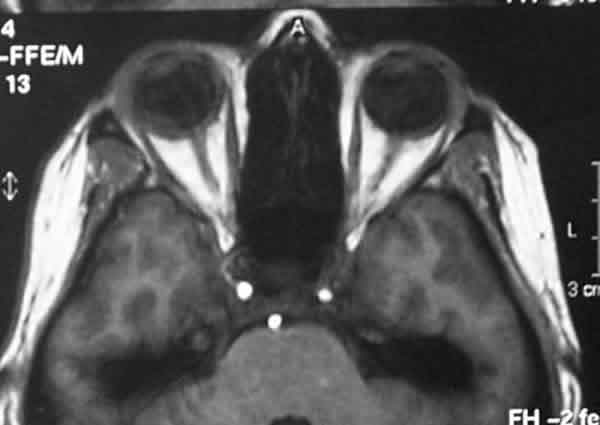

Otras pruebas diagnósticas como la angiografía fluoresceínica, la TC o la RNM raramente nos van a aportar información adicional (2) (figs 7 y 8).

Fig. 8. Secciones axiales de la TC y RNM orbitaria en la que se puede apreciar

la metástasis y el desprendimiento de retina asociados.